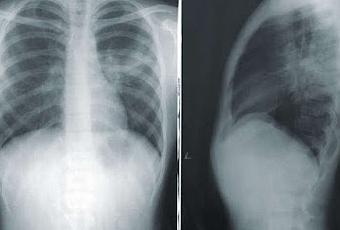

Como su nombre lo indica, sulbactam-durlobactam combina dos fármacos. El sulbactam ha sido aprobado para su uso desde 1986, pero el durlobactam es nuevo y aún no ha obtenido la aprobación, sin embargo los hallazgos han llevado a un comité unánime de expertos a recomendar a la Administración de Alimentos y Medicamentos (FDA) que apruebe el nuevo fármaco, que podría estar disponible este verano para combatir la cepa de neumonía, a menudo mortal, conocida como complejo Acinetobacter baumannii-calcoaceticus resistente a los carbapenems (ABC ), típicamente adquiridos en hospitales. Desafortunadamente, sulbactam-durlobactam no es el tipo de antibiótico de amplio espectro que podría resultar efectivo para tratar una amplia variedad de infecciones resistentes a los antibióticos, pero es muy bueno para tratar esta particularmente peligrosa, y eso es una victoria significativa.